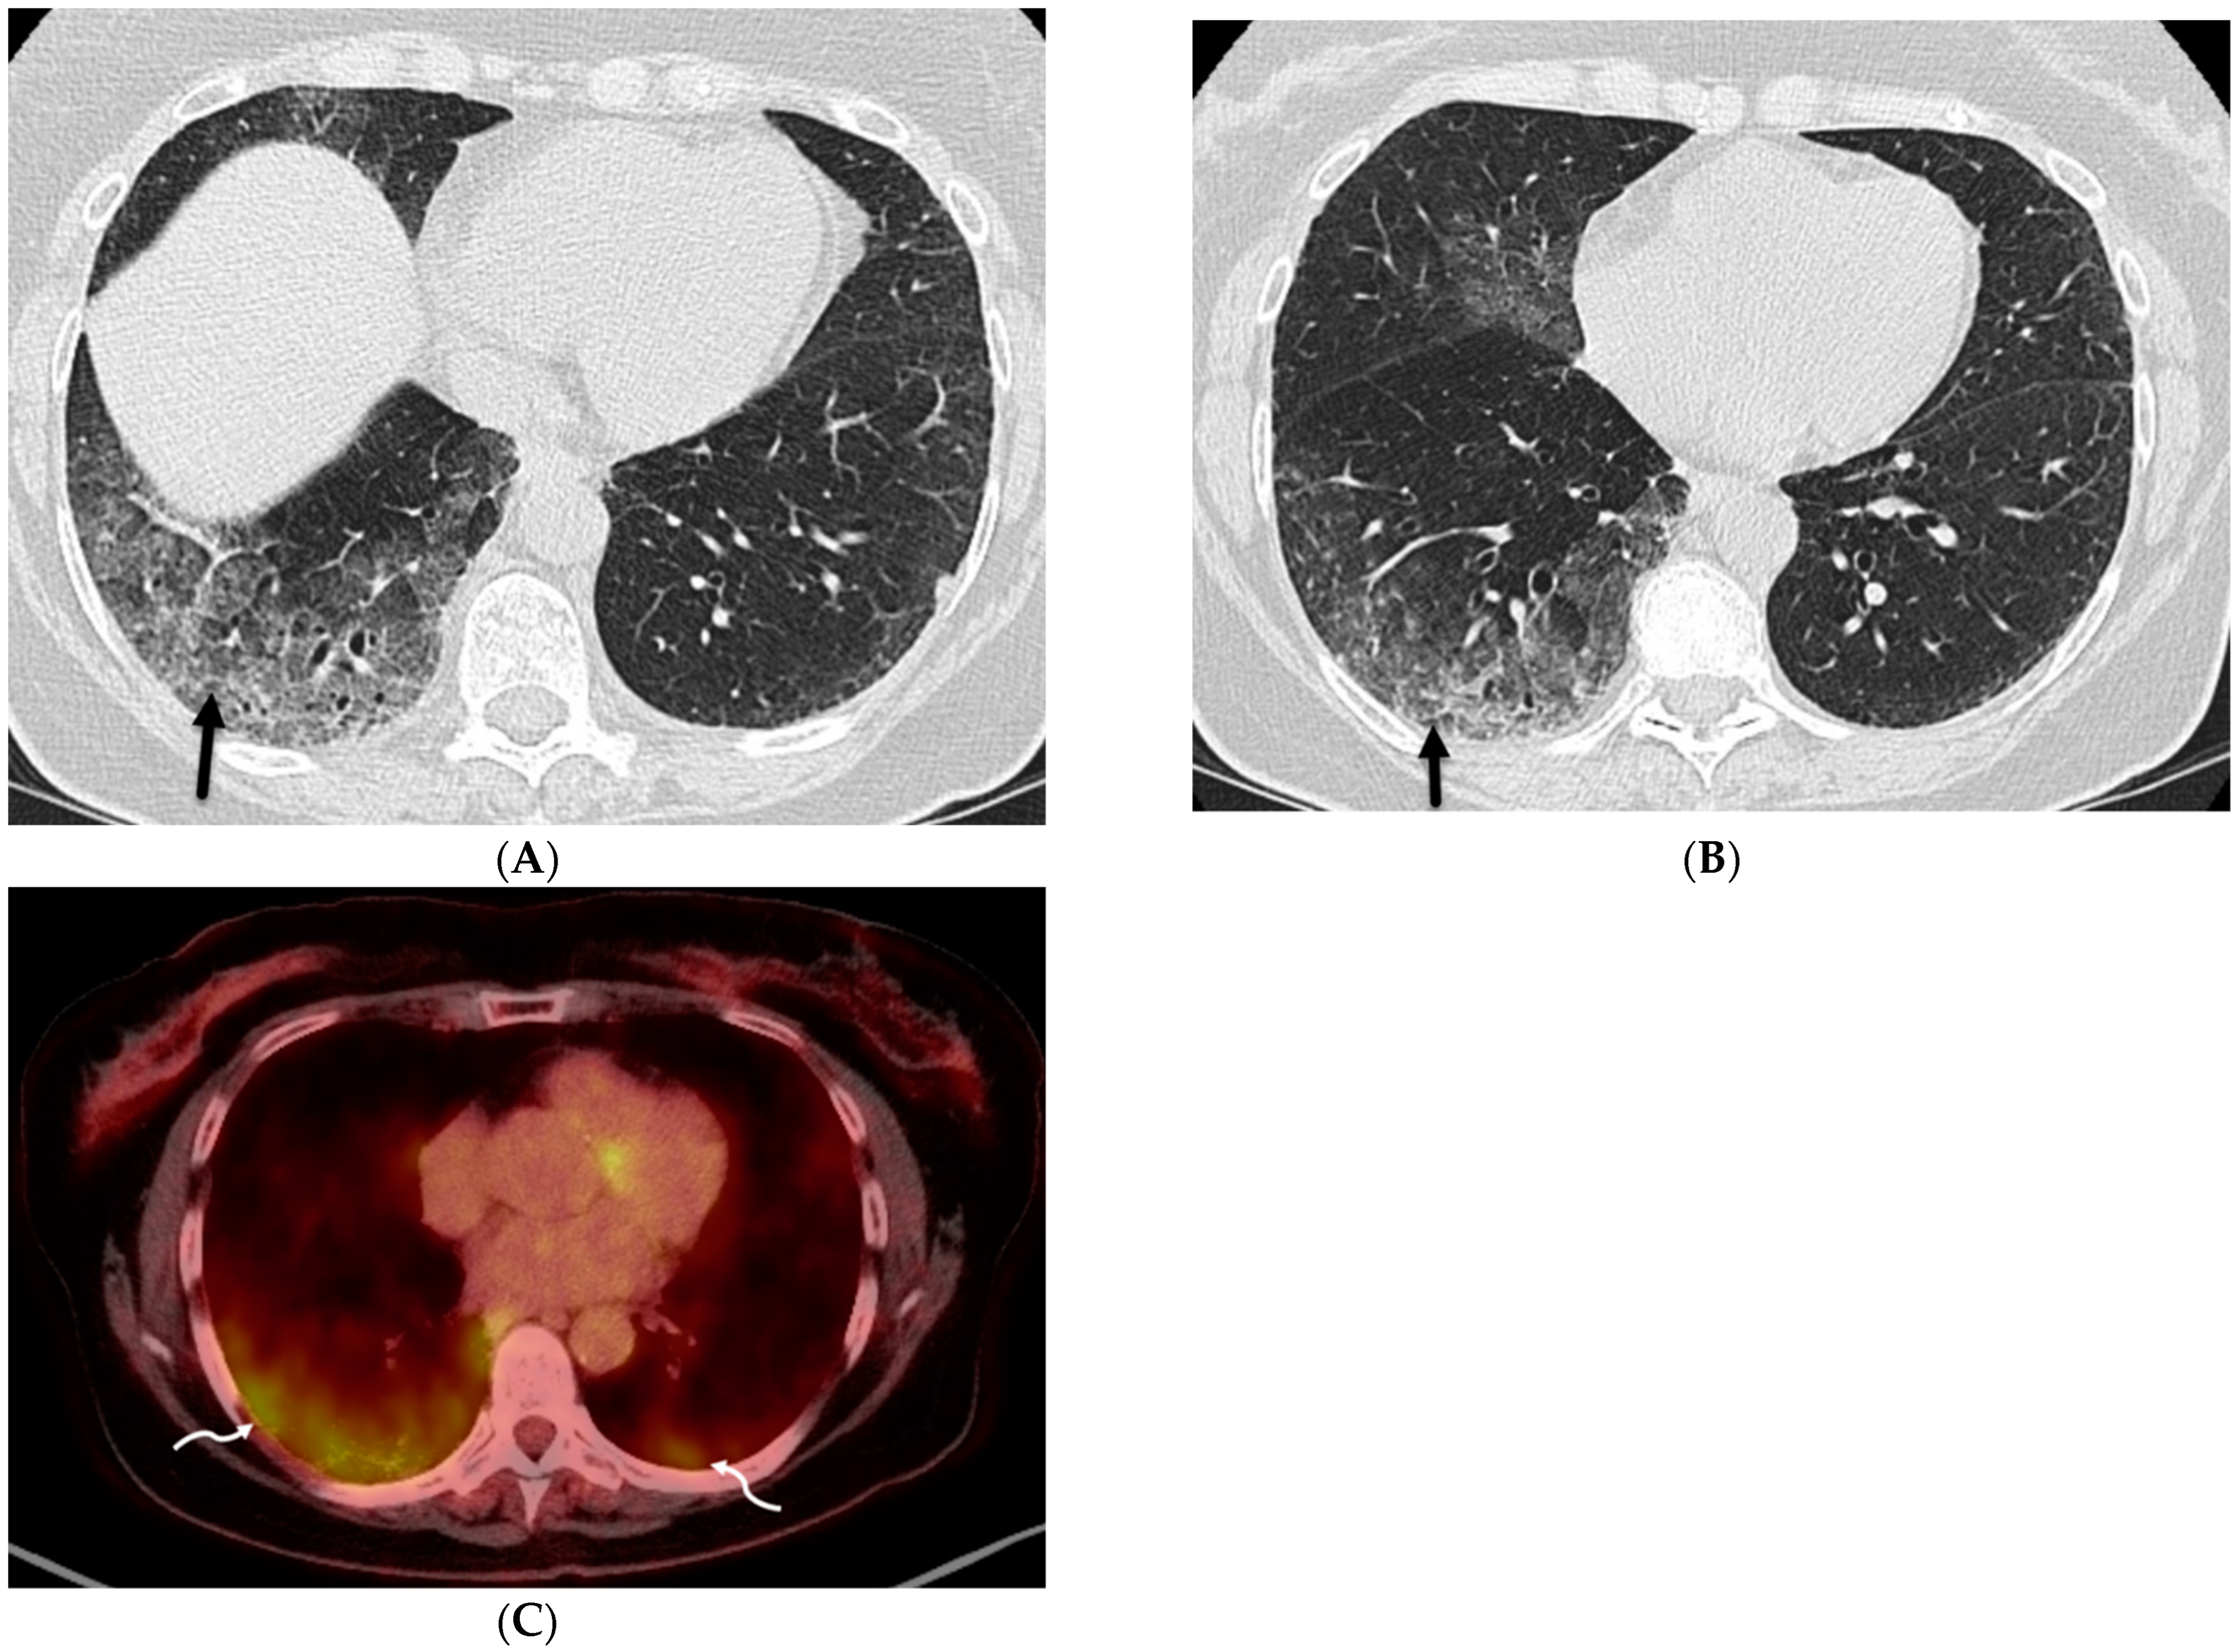

5.2. Kaposi’s Sarcoma

- Gasparetto, T.D.; Marchiori, E.; Lourenço, S.; Zanetti, G.; Vianna, A.D.; Santos, A.A.; Nobre, L.F. Pulmonary involvement in Kaposi sarcoma: Correlation between imaging and pathology. Orphanet J. Rare Dis. 2009, 4, 18. [Google Scholar] [CrossRef]